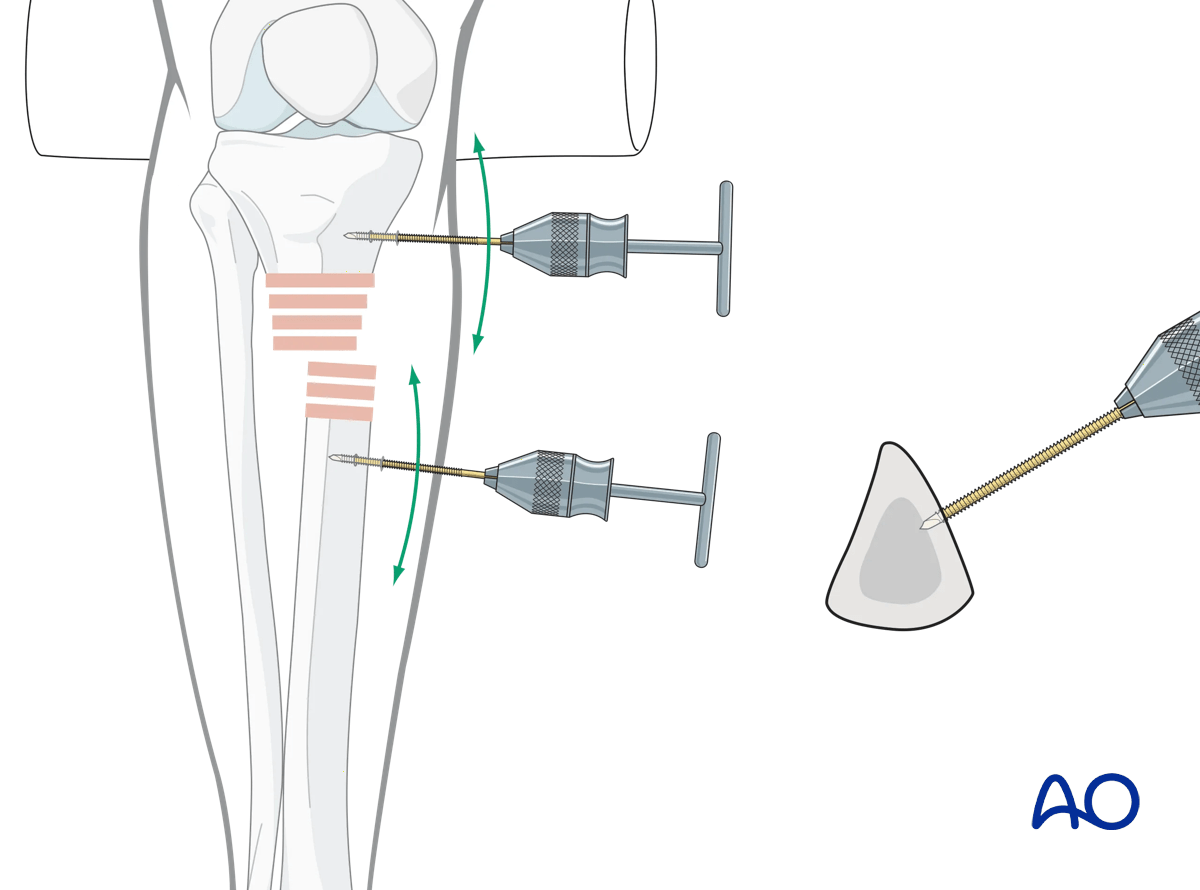

Joysticks

To aid reduction, a “joystick” (in this case a Schanz screw on a T-handled chuck) can be placed percutaneously into either or both main tibial fragments. The Schanz screw should have unicortical purchase so that it does not block the guide wire, reamer, or nail.

Suprapatellar intramedullary nailing, joysticks